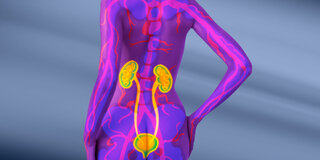

Warum Diabetes den Nieren schaden kann

Menschen mit Diabetes haben ein höheres Risiko, an Nierenleiden zu erkranken